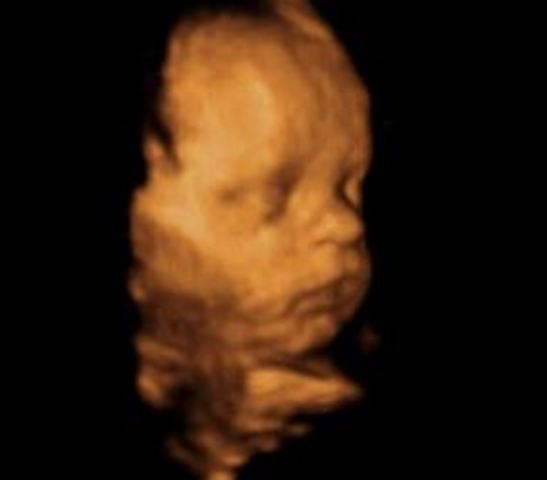

Los ojos del bebé se comienzan a abrir y cerrar regularmente pero aun cuando el color ya está genéticamente determinado este solo se podrá conocer después de los 6-8 meses de nacido. Su bebé alterna ciclos de sueño/vigilia cada 20 a 30 minutos. Los movimientos fetales se hacen muy obvios cuando usted se relaja, sentada o acostada, especialmente durante la noche. Los rasgos faciales son muy claros